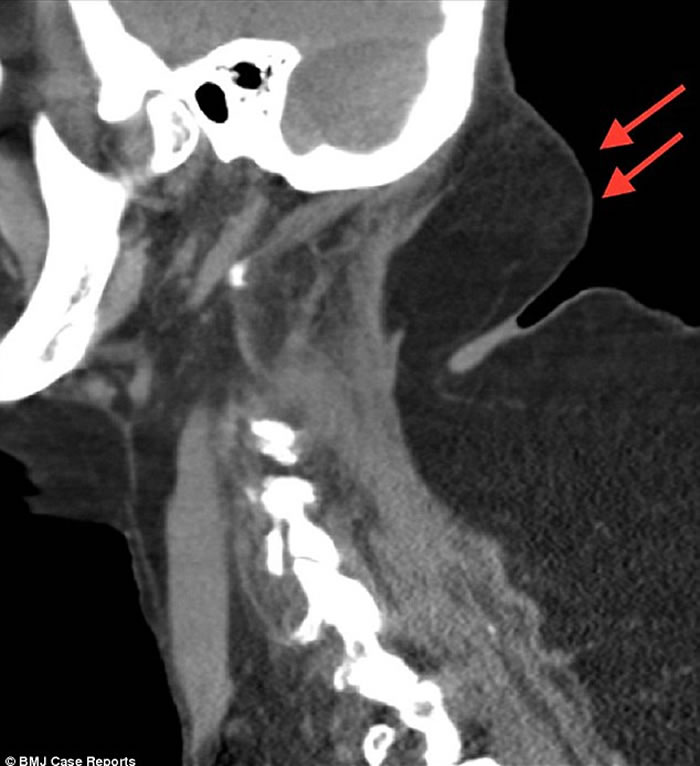

该名六旬妇人背部隆起(箭嘴示),犹如长有驼峰。

经检查后,发现病人患上罕见的马德龙病。

(蜘蛛网报道)英国一名饮酒长达40年的64岁妇人,因长时间酗酒,导致背部隆起,长出一个类似驼峰的物体,于是到医院求医。医生看到妇人的颈部及手臂同样有囊肿后,到网上查证,发现她患上罕见的马德龙病(Madelung disease)。

根据《英国医学期刊》披露,该名妇人当日到来求诊时,意识混乱、无法告知时间,双手双脚亦无力。医生其后发现病人的上半身遍布囊肿,经血液测试后,确认她患上酮酸中毒。酮酸中毒一般见于患上一型糖尿病的人士,情况罕见并可致命。